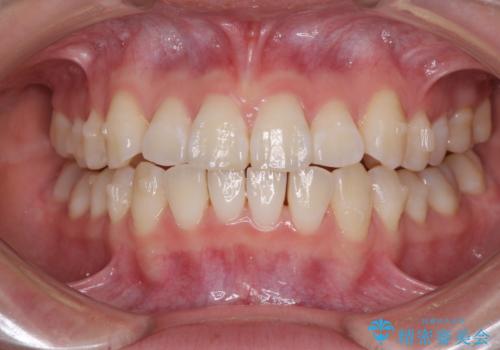

- 海外留学の予定があるが、学生のうちに歯列を整えたいとのことで来院された患者様です。

前歯にデコボコがあり、口元がやや突出した印象があったため、IPR(歯と歯の間を削る)と親知らずを抜歯した上での歯列全体の後方移動をメインに、インビザラインを用いて矯正治療を行うこととしました。

年に一度、夏休みの時期にしか帰国できないため、帰国のタイミングに合わせてマウスピース交換スケジュール治療計画としたため、3年半という期間を要しました。

留学先でもしっかりとマウスピースの装着を実践してくださったので、ご本人の満足のいく仕上がりとなりました。